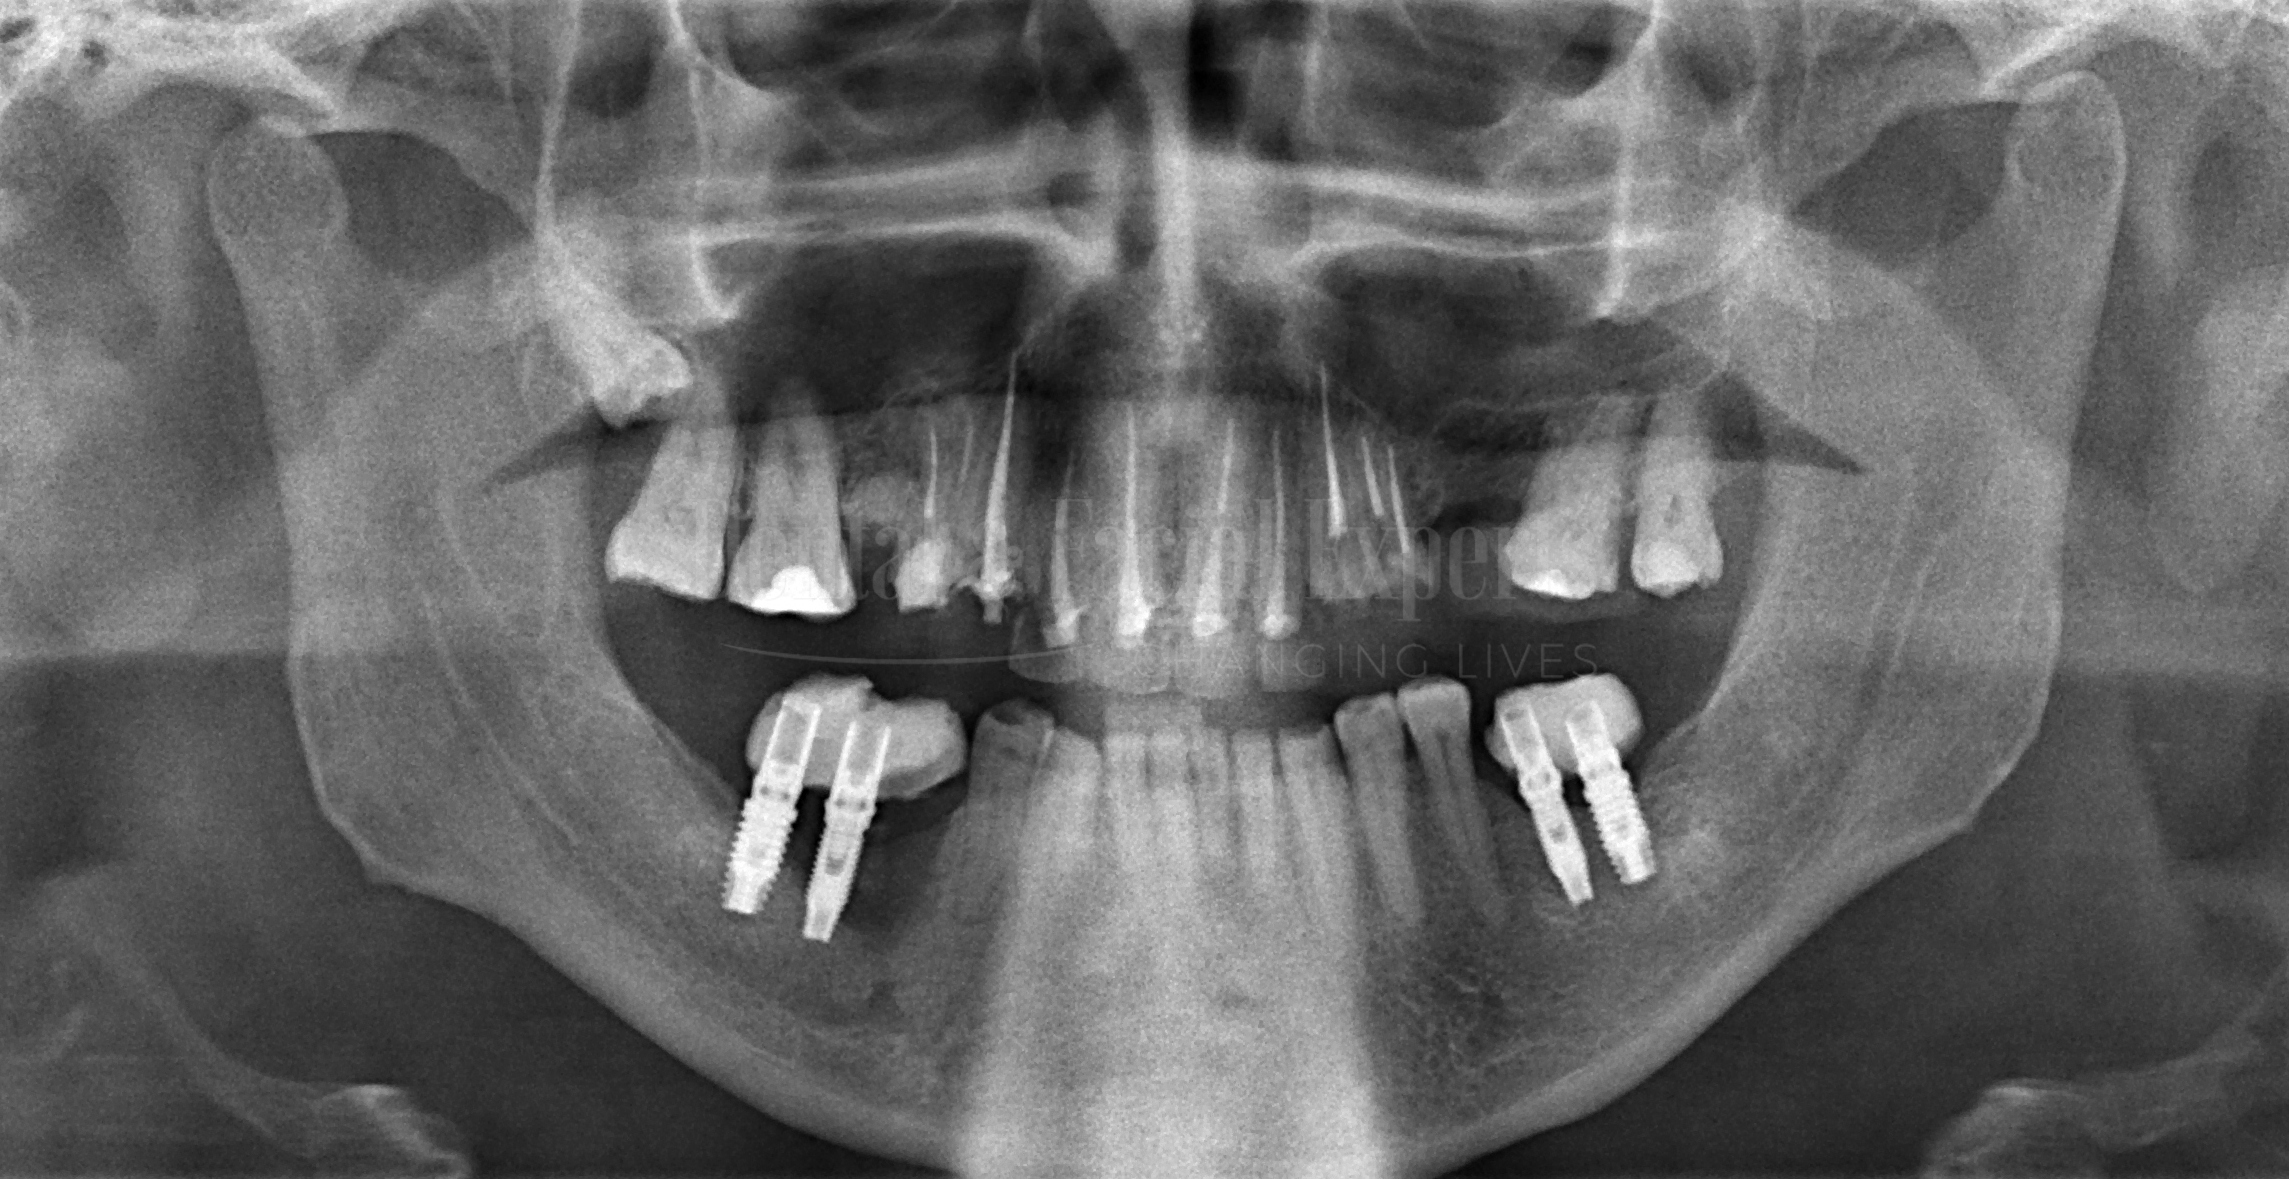

JOSE-2-Cópia-500x376

JOSE 2

Medidas Sidexis Pre

Medidas Sidexis Post